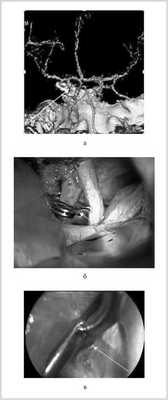

Рис. 2. Клипирование аневризмы офтальмического сегмента левой внутренней сонной артерии (ВСА). а — магнитно-резонансная ангиограмма, вид сзади: аневризма офтальмического сегмента левой ВСА (указано стрелкой); б — вид через микроскоп: аневризма ВСА клипирована фенестрированной клипсой (указано стрелкой); в — вид через эндоскоп: клипса перекрывает шейку АА у основания (указано стрелкой), ствол ВСА не деформирован.

У больной с АА бифуркации БА (рис. 3) ВЭСА позволила уточнить локализацию шейки АА и контралатеральных задней мозговой и верхней мозжечковой артерий, после чего стало возможным клипирование АА без риска нарушения кровотока по указанным сосудам (рис. 4).

Рис. 3. Левосторонняя вертебральная ангиограмма, боковая проекция с разворотом больной П., 50 лет: АА бифуркации БА. 1 — базилярная артерия, 2 — аневризма бифуркации базилярной артерии, 3 — спинка турецкого седла.

Рис. 4. Клипирование аневризмы бифуркации базилярной артерии больной П., 50 лет. а — правосторонняя птериональная краниотомия, доступ через ретрокаротидный промежуток (вид через микроскоп); б — вид через эндоскоп с тубусом 30° через ретрокаротидный промежуток. 1 — базилярная артерия, 2 — задняя мозговая артерия, 3 — шейка аневризмы (обозначена пунктиром), 4 — шпатель на базальной поверхности лобной доли мозга, 5 — шпатель на медиальной поверхности височной доли мозга, 6 — контралатеральная задняя мозговая артерия, 7 — контралатеральный глазодвигательный нерв.